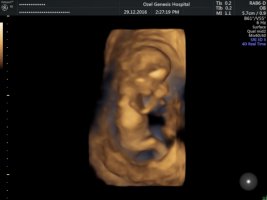

Merhaba , nub teorisine göre cinsiyet tahmini yapan arkadaşımızın dediği gibi resimlerinizin net olması gerekmektedir. Doktorunuz çekim anında görüntüyü net olarak görebilmektedir. Elinize verilen görsel doktorun verdiği görüntü kadar net olmayabilir..Durumu değerlendirilen arkadaşların yolladığı gibi lütfen görselleriniz net olsun.